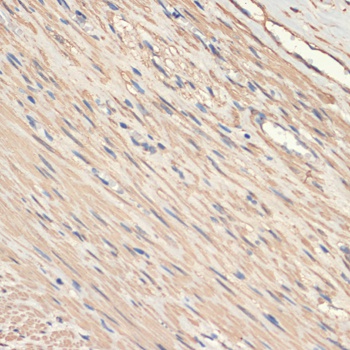

IHC: Formalin-fixed, paraffin-embedded human colon carcinoma stained with SMMHC antibody (MYH11/923).

IHC: Formalin-fixed, paraffin-embedded human Leiomyosarcoma stained with SMMHC antibody (MYH11/923).

IHC: Formalin-fixed, paraffin-embedded human breast carcinoma stained with SMMHC antibody (MYH11/923).

IHC: Formalin-fixed, paraffin-embedded human angiosarcoma stained with SMMHC antibody (MYH11/923).